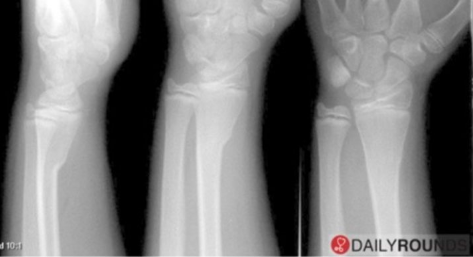

X-ray showing compression on one side of the radius causing the other side to bend/ buckle suggests a _____ fracture.